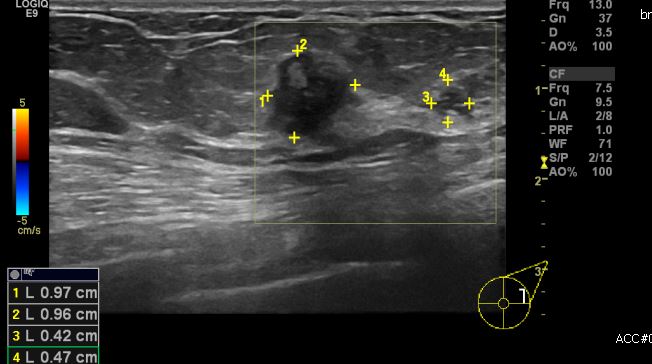

좌측 만져지는 멍우리로 내원하신 50대 여성분으로  좌측 2시30분 방향에 만져지는

멍우리 중심핵생검 시행하여 좌측 침윤성 유관암 진단되었습니다.